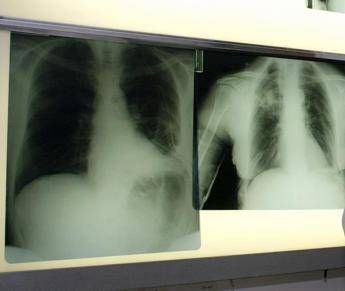

Cancro polmone a piccole cellule, ok Ue a tislelizumab

(Adnkronos) – BeOne Medicines, azienda oncologica globale, ha annunciato oggi che la Commissione europea ha approvato tislelizumab in combinazione con chemioterapia a base di etoposide e platino come trattamento di prima linea dei pazienti adulti con tumore del polmone a piccole cellule di stadio esteso (Es-Sclc). "Il tumore del polmone a piccole cellule in stadio esteso è notoriamente difficile da trattare per la sua natura aggressiva e necessita di nuove opzioni terapeutiche – afferma Silvia Novello, presidente di Women against Lung Cancer in Europe (Walce), direttore Oncologia medica all'Ospedale San Luigi Gonzaga di Orbassano e professore ordinario di Oncologia medica all'Università degli Studi di Torino – I risultati dello studio Rationale-312 mostrano che tislelizumab più chemioterapia ha migliorato la sopravvivenza rispetto al trattamento con placebo più chemioterapia, evidenziando la capacità di offrire migliori risultati per i pazienti eleggibili". L'approvazione nel tumore del polmone a piccole cellule di stadio esteso (Es-Sclc) – riporta una nota – si basa sui risultati di Rationale-312 (NCT04005716), uno studio multicentrico di fase 3 randomizzato, in doppio cieco, controllato con placebo, mirato a valutare l'efficacia e la sicurezza di tislelizumab in combinazione con platino (cisplatino o carboplatino a scelta dell’investigatore) più etoposide, come trattamento di prima linea dei pazienti adulti con Es-Sclc. Lo studio, che ha randomizzato 457 pazienti, ha raggiunto l'endpoint primario, mostrando un miglioramento statisticamente significativo e clinicamente rilevante della sopravvivenza globale (Os) con tislelizumab in combinazione con chemioterapia, rispetto a placebo più chemioterapia nella popolazione intent-to-treat (Itt). Come riportato sul 'Journal of Thoracic Oncology', all'analisi finale prevista dal protocollo la sopravvivenza mediana è risultata di 15,5 mesi per tislelizumab con chemioterapia rispetto a 13,5 mesi per placebo più chemioterapia, con una riduzione del 25% del rischio di morte. Tislelizumab più chemioterapia è stato generalmente ben tollerato e non sono stati identificati nuovi segnali di sicurezza. "In meno di 2 anni, tislelizumab è stato approvato in 4 patologie distinte nell'Ue, sottolineando la sua capacità di produrre miglioramenti della sopravvivenza clinicamente significativi e un profilo di sicurezza ben caratterizzato in vari tipi di tumori – dichiara Mark Lanasa, Chief Medical Officer, Solid Tumors in BeOne Medicines – La nostra comprovata esperienza con le registrazioni di tislelizumab in 45 Paesi rafforza il nostro impegno a offrire trattamenti innovativi al maggior numero possibile di persone affette da cancro". L'approvazione – prosegue la nota – si basa anche sui dati di sicurezza aggregati provenienti da più di 3.900 pazienti trattati con tislelizumab sia in monoterapia (n=1.952) che in combinazione con chemioterapia (n=1.950) al regime di dosaggio approvato. Le reazioni avverse più comuni di grado 3 o 4 (≥ 2%) con tislelizumab in combinazione con chemioterapia sono state neutropenia, anemia, trombocitopenia, iponatriemia, ipocalcemia, fatigue, polmonite, linfopenia, eruzione cutanea, diminuzione dell’appetito, aumento di aspartato aminotransferasi, e aumento di alanina aminotransferasi. Oltre al tumore del polmone a piccole cellule di stadio esteso, tislelizumab è approvato nell'Ue per 3 indicazioni nel tumore del polmone non a piccole cellule (Nsclc) nei setting di prima e seconda linea, come trattamento di prima linea dei pazienti eleggibili con carcinoma esofageo a cellule squamose non resecabile (Escc), nell'adenocarcinoma gastrico o della giunzione gastroesofagea (G/Gej) in combinazione con chemioterapia, e come trattamento di seconda linea nel carcinoma esofageo a cellule squamose localmente avanzato o metastatico, non resecabile dopo una precedente chemioterapia a base di platino. —salutewebinfo@adnkronos.com (Web Info)